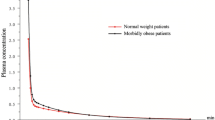

The prediction-corrected VPC plots for dexmedetomidine PK. The VPC plots show the simulation-based 95% confidence intervals around the 10th, 50th, and 90th percentiles of the PK data in the form of blue (50th) and gray (10th and 90th) areas. The corresponding percentiles from the prediction corrected observed data are plotted in black color

The model-building process started with a two-compartment model and proportional residual error model based on literature findings. This model turned out to be the best to describe the data. The simpler one-compartmental model and more complex three-compartment model were not superior based on the applied criteria. Similarly the additive or combined additive and proportional error models did not lead to model improvements based on AIC criterion. Supplemental Fig. 1S shows typical goodness-of-fit plots for the final model. The individual predictions are close to that of the experimental data with no major systematic bias, indicating good performance of the model, which is also confirmed by other goodness-of-fit plots. The VPC for the dexmedetomidine concentration were used to assess the simulation properties of the model. Figure 2 shows the results. VPC plots indicate that both the central tendency of the data and the variability at a particular sampling time were recaptured well. There are no major misspecifications in that graph.